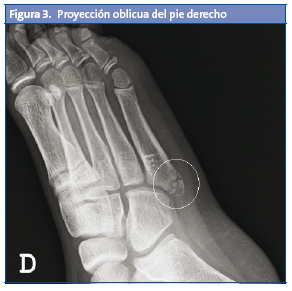

Posteriormente, es valorado por su pediatra, que observa tumefacción no dolorosa también en el pie izquierdo; al tratarse de un preadolescente que realiza deporte de forma habitual, sin un antecedente traumático conocido, y ante la sospecha de posible apofisitis, decide realizar una radiología bilateral oblicua, que presenta una imagen de fragmentación en la base del quinto metatarsiano de ambos pies (Figs. 2 y 3).

La confirmación diagnóstica nos la proporciona la radiología oblicua4,5, ya que la anteroposterior y la lateral pueden no mostrar con claridad el centro de osificación. En dicha radiografía oblicua, podemos observar un aumento o fragmentación de la epífisis y un ensanchamiento de la unión cartilaginosa. La proyección oblicua y la radiología comparativa de ambos pies son de gran utilidad para la confirmación diagnóstica.